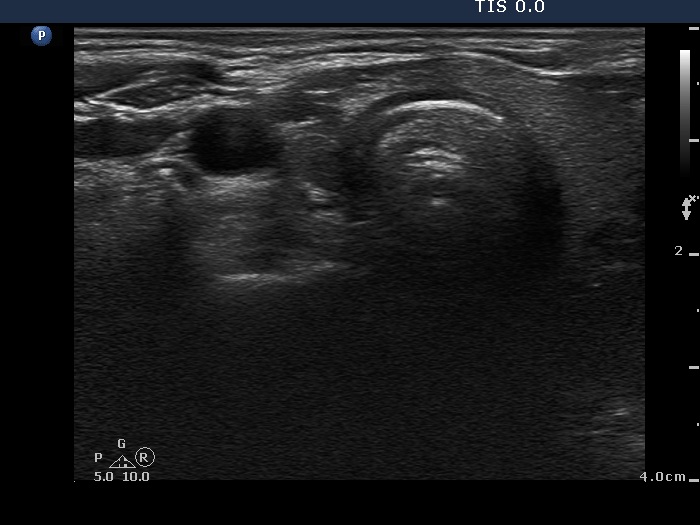

Clinical presentation: A 55-year-old woman was referred for aspiration cytology. She has a right lobectomy 10 years ago. At that time, a relatively small cystic nodule was already in the left lobe which was not operated. She noticed a lump in the left thyroid several weeks before the present examination.

Palpation: an elastic nodule in the left lobe.

Ultrasonography. There was no parenchyma in the right the thyroid bed. The left lobe was minimally hypoechogenic and had a large, multichambered cystic nodule. There were both hyperechogenic lines and granules within the dorsal wall of the cystic areas. The solid part was moderately hypoechogenic.

Comment. Most of the hyperechogenic figures correspond to posterior back wall enhancement. There were a few colloid crystals within the cystic fluid.